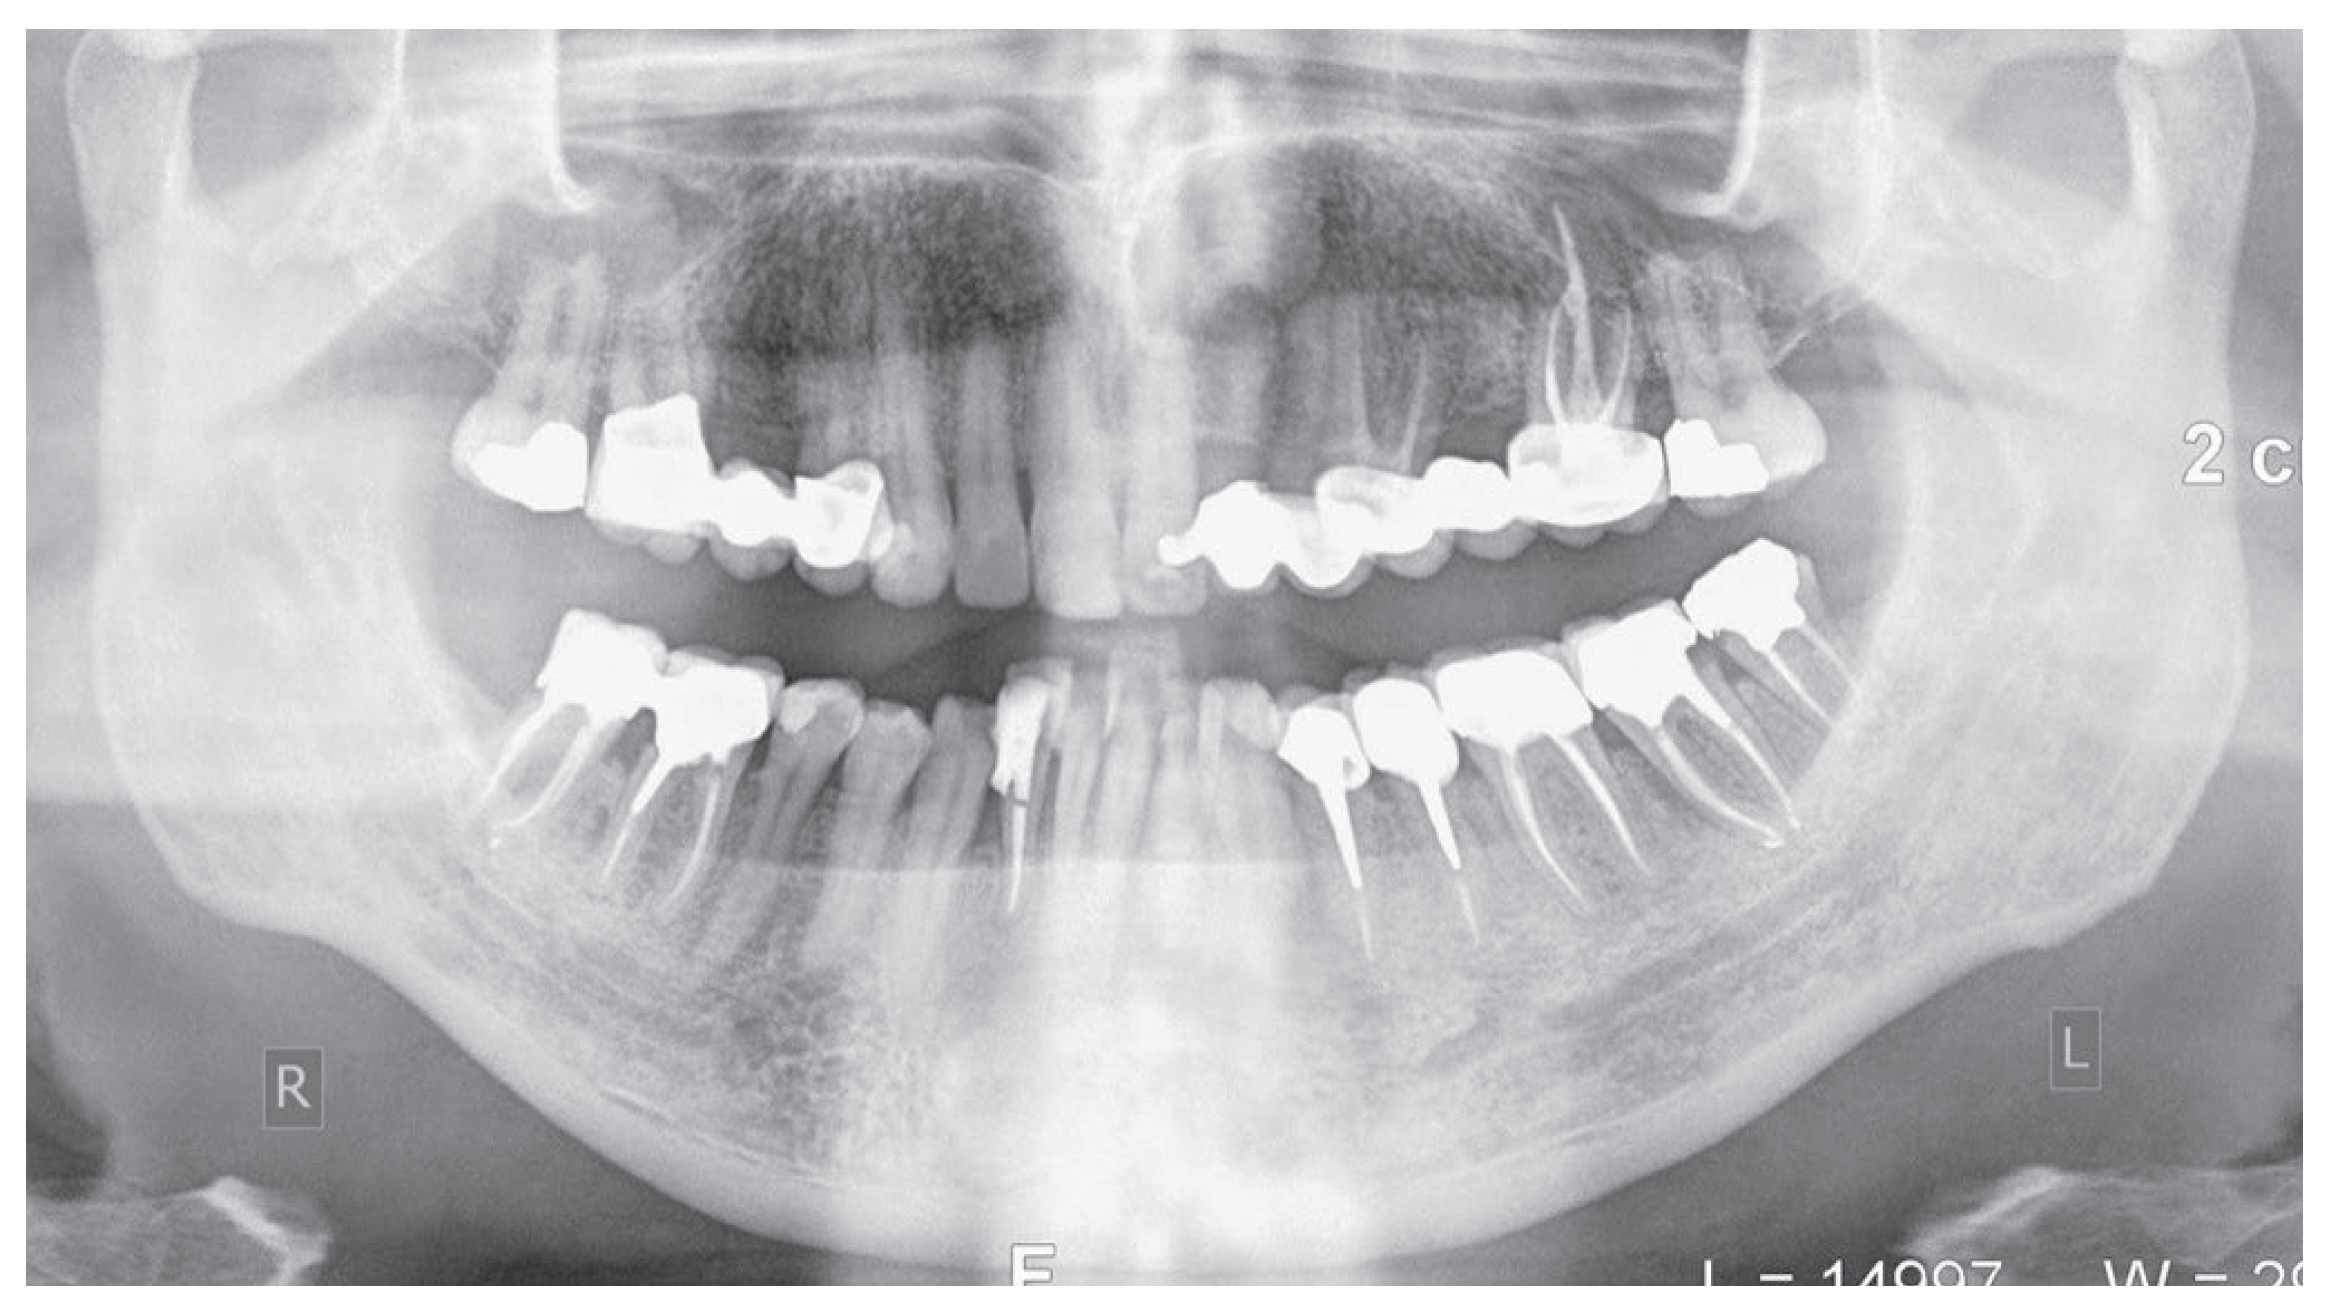

From radiographic examination with OPT (Figure 1) a moderate periodontal bone loss on the lower right side of the patient was observed.

Figure 1. Initial OPT X-Ray.